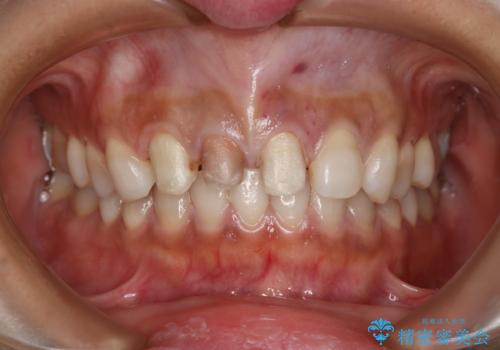

- 1週間ほど前に自転車で転倒して前歯をぶつけた後、歯の色が変わっていることが気になり受診された方です。診察の結果、失活及びエナメル質に多数の亀裂が認められたため、根管処置およびセラミッククラウンによる治療を行いました。元々右上2番目の歯の形が気になっていたとの事で、左右対称の形に近づけるように補綴しました。

左上1番目の歯は失活していませんでしたが、歯の表面に多数の亀裂が認められました。患者様のご希望により、前歯3本をまとめて補綴処置することとなりました。土台となる歯質の色が異なる状態でしたが、熟練した技工士さんの技術により3本とも同じ色味になるように仕上げていただきました。色味、形態ともに自然な被せ物に大変喜んでいただけました。